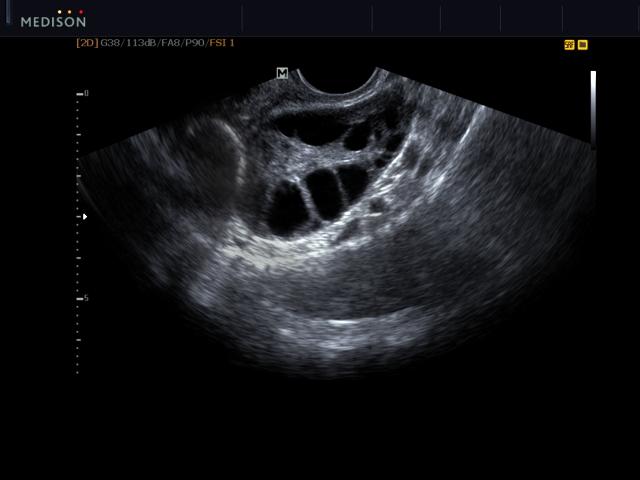

Яичник с фолликулами, ТВЭ